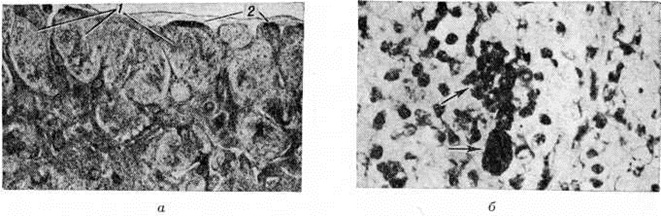

Патогистология. Капсула лимфатических, узла сохранена, периаденит отсутствует. Структура узла, как правило, не нарушена. Иногда она может быть стёртой. В корковом веществе — скопление ретикулярных клеток с веерообразно расположенными новообразованными капиллярами. Синусы сохранены, хотя нередко бывают замаскированы воспалительным инфильтратом, состоящим из лимфоцитов и в меньшей степени эозинофилов, нейтрофилов и плазматических клеток. Лимф, фолликулы могут быть гиперплазированы (рисунок, а), однако в периферических зонах лимфатических, узла они чаще кажутся атрофичными в результате их сдавливания ретикулярными клетками. В большинстве случаев часть ретикулярных клеток содержит фагоцитированные меланин, липиды, иногда гемосидерин. Меланин обнаруживается и внеклеточно (рисунок, б).

Рис

Микропрепараты лимфатического узла больного липомеланотическим ретикулематоза — обширная ретикулярная гиперплазия (1) и сохранившаяся капсула (2), × 13; б — отложения меланина внутри и внеклеточно (указан стрелками), × 750.